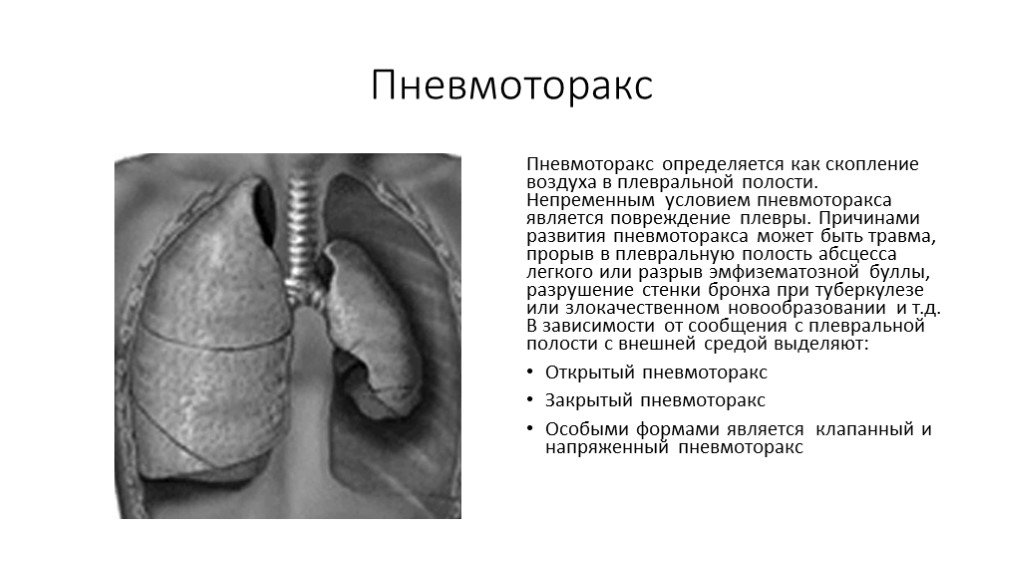

Схемы дыхания: Пневмоторакс на изображениях